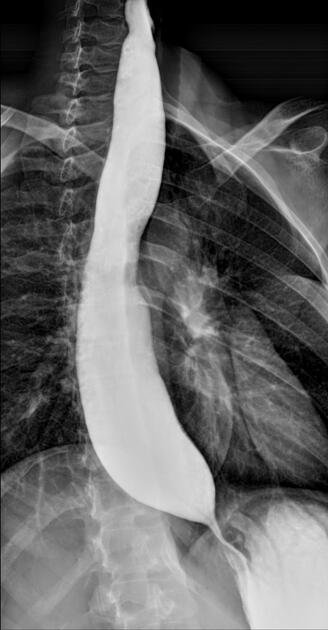

A middle-aged patient presents with dysphagia for liquids. A barium esophagogram is shown. What is the diagnosis?

Explanation: ***Achalasia*** - Barium esophagogram shows the classic **"bird-beak" sign** with a dilated esophagus and smooth tapering at the gastroesophageal junction. - **Dysphagia for both liquids and solids** is characteristic, caused by failure of the **lower esophageal sphincter** to relax properly. *Diffuse esophageal spasm (DES)* - Barium study would show a **"corkscrew" pattern** with multiple simultaneous contractions, not the smooth tapering seen here. - Typically causes **chest pain** rather than progressive dysphagia, and liquids are usually tolerated better than solids. *Nutritional causes of esophageal dysfunction (NCE)* - Would not produce the characteristic **bird-beak appearance** on barium swallow studies. - Usually associated with **vitamin deficiencies** (B12, folate) and presents with more generalized symptoms rather than isolated dysphagia. *Esophageal cancer* - Barium study would show an **irregular filling defect** or **apple-core lesion** rather than smooth tapering. - Typically presents with **progressive dysphagia** starting with solids then progressing to liquids, opposite to the pattern in achalasia.